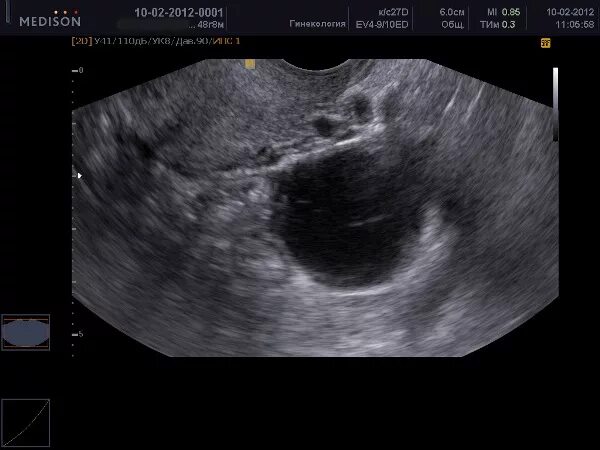

Яичник 8 см